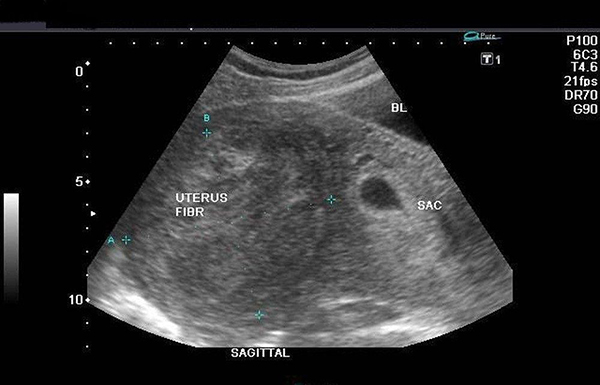

– U xơ tử cung:

Những khối u nhỏ của u xơ sẽ có mặt và phát triển lên từ lớp cơ của tử cung. Từ những hình ảnh thu được từ đầu dò, có thể nhận thấy tình trạng, kích thước hiện tại của các u xơ, từ đó thấy được mức độ nguy hiểm mà chỉ định có nên mổ hay không. Bệnh lý này xuất hiện ở bất kỳ độ tuổi nào, tuy nhiên trong khoảng từ 35 – 50 khả năng mắc bệnh chiếm tỷ lệ cao hơn.

Phát hiện u xơ tử cung qua siêu âm đầu dò